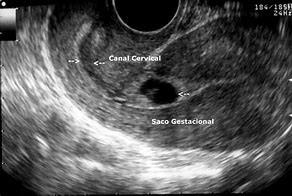

• Esnecesarioqueexistaunembarazo

• Que exista la interrupción del proceso fisiológico del embarazo, con muerte o destruccióndelaconcepción

• Es necesario que se emplee un medio idóneo para provocar el aborto, ya sea quirúrgicos,químicos,mecánicosymorales.